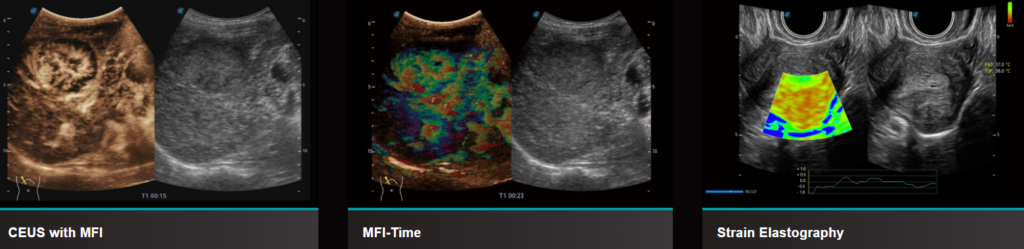

Функції УЗД системи S50 Elite

- Micro F, забезпечує інноваційний метод розширення діапазону видимого потоку при ультразвуковому дослідженні, особливо для візуалізації гемодинаміки крихітних судин.